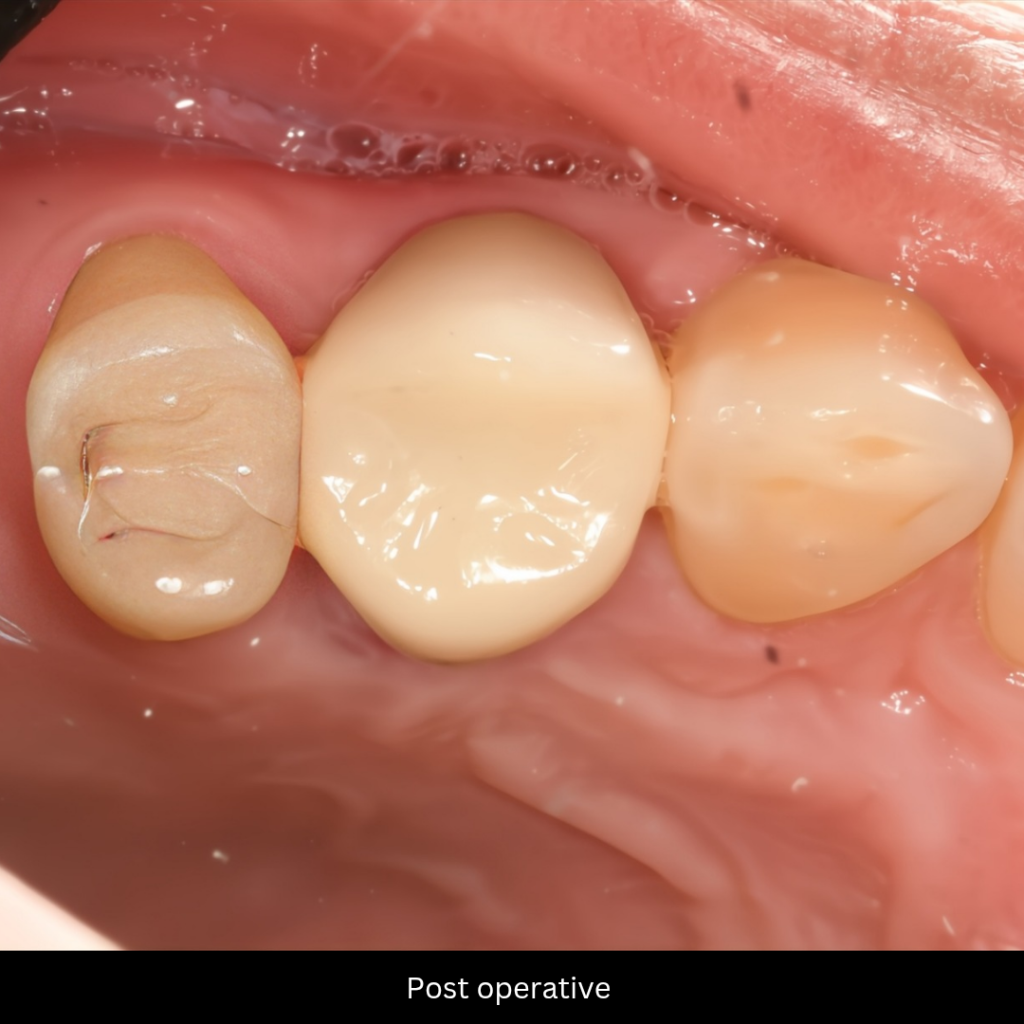

Delivery and Cementation: After a short turnaround time of 4 days, the definitive crown was delivered, verified for marginal fit, occlusion, and aesthetics.

post operative zircon crown

before and after